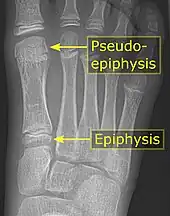

It is common in children to have a pseudo-epiphysis of the first metatarsal.[5]